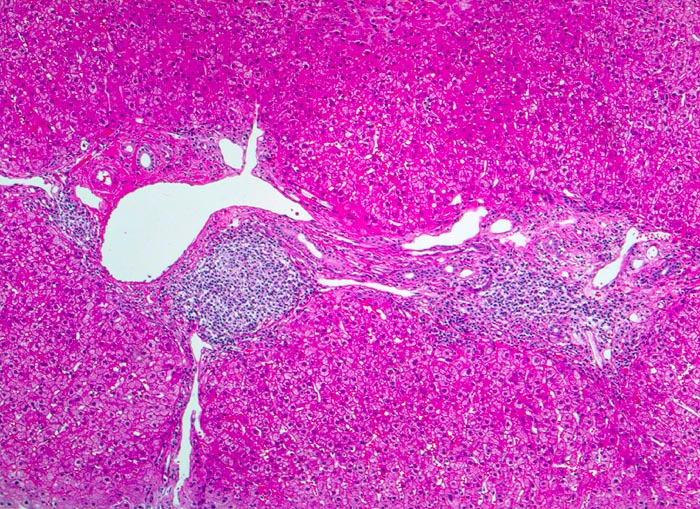

Morphologische Merkmale:

• Dichte mononukleäre portale und lobuläre Entzündungsinfiltrate mit Ausbildung von Lymphfollikeln in den Portalfeldern.

• Übergreifen der Entzündung auf das Parenchym (=Interface oder Grenzzonenhepatitis).

• Abgerundete hypereosinophile apoptotische Hepatozyten (Councilman-Körperchen).

• Geringe Portalfeldfibrose. Das sollte der Kliniker dem Pathologen mitteilen: